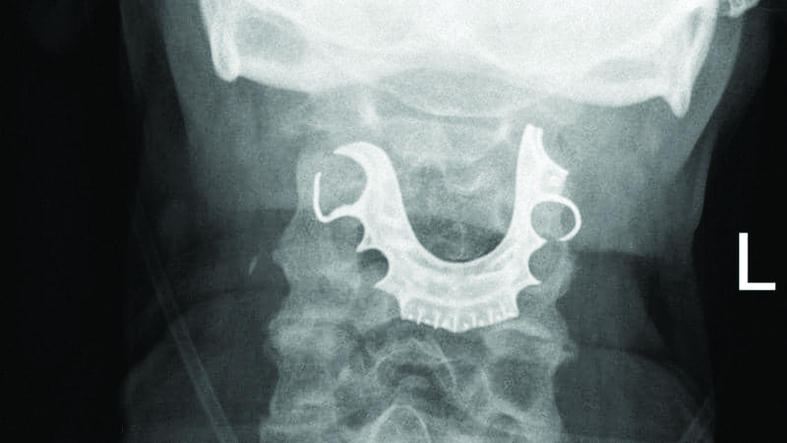

وبعد ستة أيام من الجراحة، عاد الرجل إلى المستشفى بعدما اكتشف وجود دماء في فمه، كما شعر بآلام ووجد صعوبة في ابتلاع الطعام، حيث خضع للفحص، واكتشف الأطباء وجود جسم نصف دائري في حلقه حول الأحبال الصوتية، ما أدى إلى التهابات داخلية، وأثبتت الأشعة الضوئية أن هذا الجسم هو طاقم الأسنان.

واضطر الأطباء إلى إجراء جراحة عاجلة للرجل لانتزاع الأسنان المستعارة، وقضى في المستشفى ستة أيام إضافية، فيما كشفت مجلة "بي إم جي كايس ريبورت" الطبية، أن الرجل اعترف بأنه فقد الطاقم قبيل الجراحة.